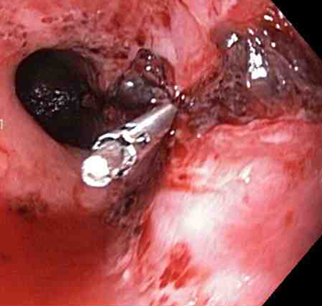

A through-the-scope clip deployed in the center of the lesion (no previous epinephrine was infused in this case)

From the collection of Juan Carlos Munoz, MD, University of Florida